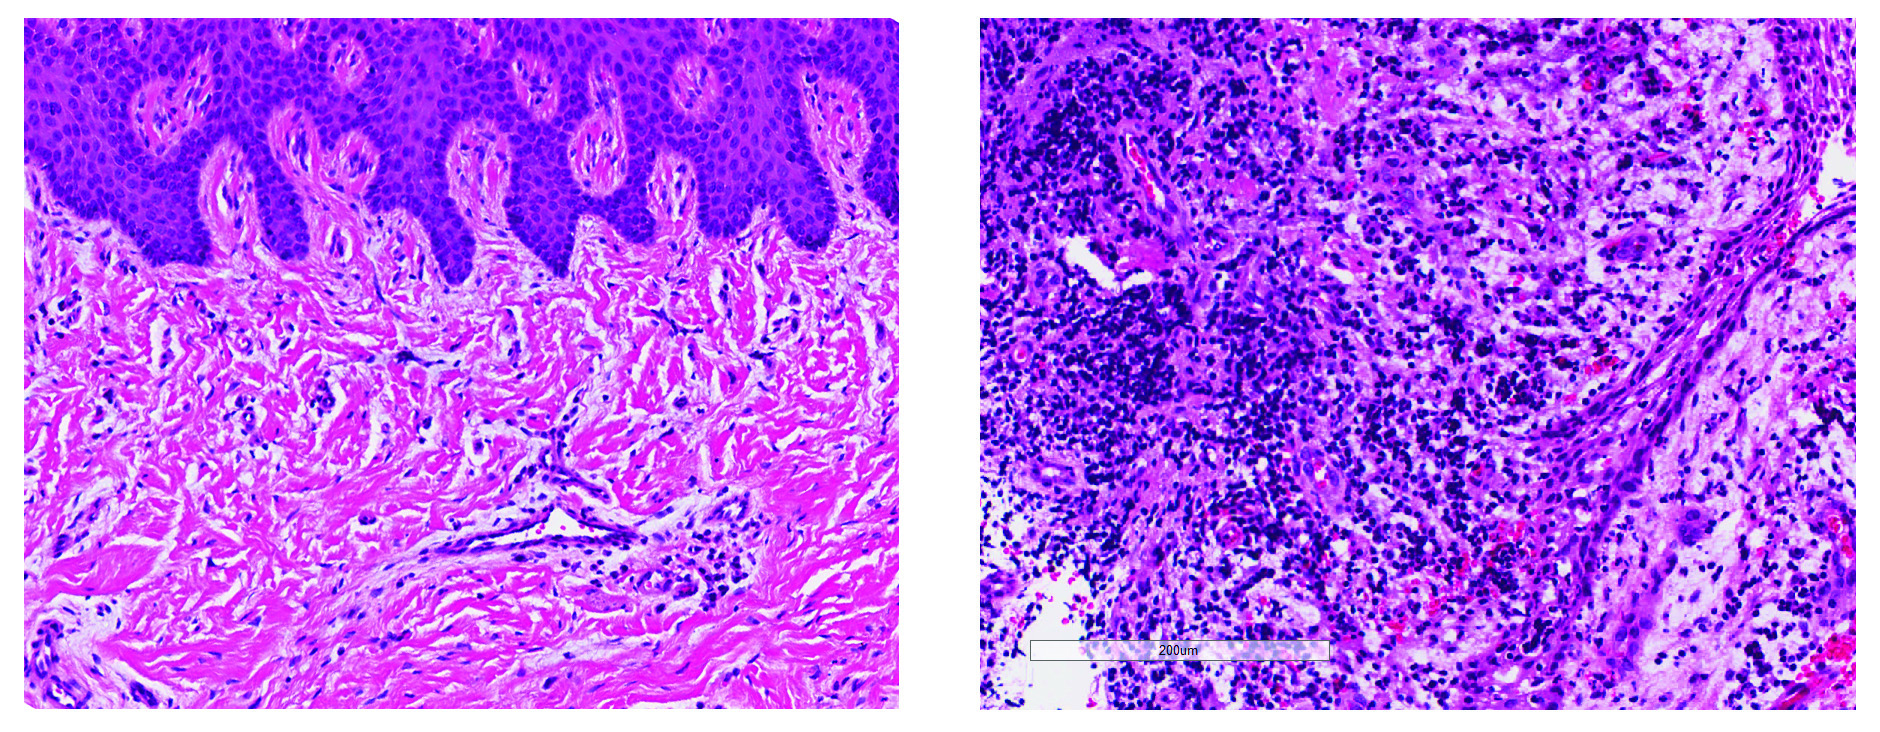

Image contrasts healthy gum tissue (left) and chronic periodontal disease (right).

Compared to healthy gum tissue (left), chronic periodontal disease (right) is marked by a buildup of unhealthy bacteria and large numbers of immune cells, leading to severe inflammation and bone loss. ǀ NIDCR/NIH

healthy gums (left), diseased gums (right)

Compared to healthy gums (left), diseased gums (right) show accumulation of immune cells (purple dots) and breakdown of tissue (pink). ǀ NIDCR/NIH

targeted approaches to modulate — and control — the destructive inflammation that drives periodontal disease.